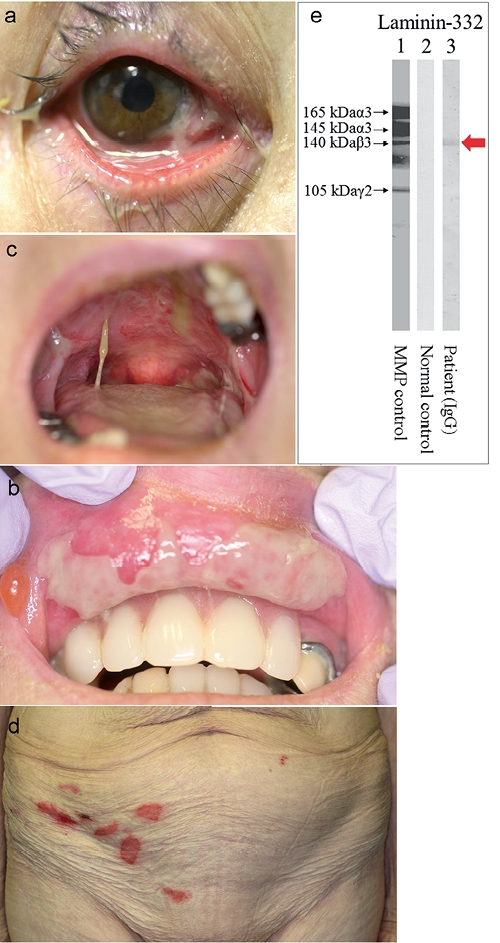

Characteristic features:

almost same features as benign mucous membrane pemphigoid and pemphigus vulgaris

C3 and circulating autoantibodies is detectable in indirect immunofluorescent test

autoantibody against BP antigen at lamina lucida